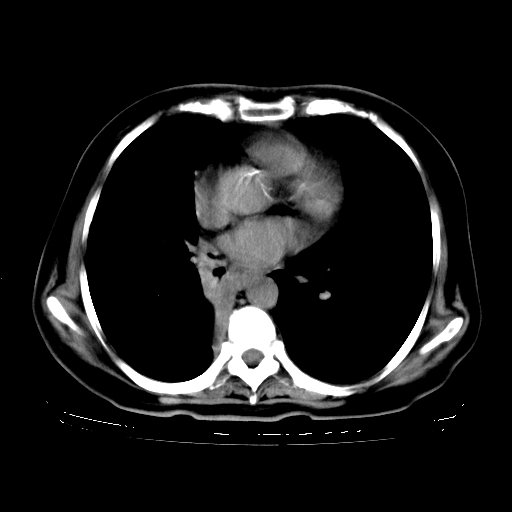

女,70岁,咳嗽、咳痰一个月,低热一周。

1、右肺占位,考虑周围型ca 。

2、右下肺软组织密度肿块影,考虑肺隔离征。

3、两肺肺结核(右肺下叶背段及左肺)。

4、主动脉夹层。

5、右侧少量胸腔积液。